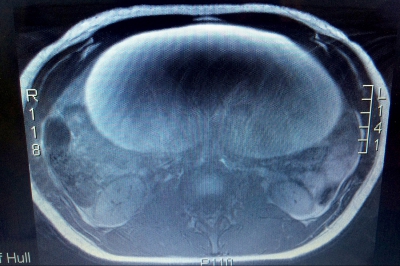

Când i-au făcut radiografie însă, au fost şocaţi. În realitate, tânăra avea o tumoare malignă de mărimea unui pepene, scrie The Sun.

"Când medicii au văzut radiografia au spus pur şi simplu 'wow' - au fost cu adevărat terifiaţi să vadă cât de mare era tumoarea. Avea dimensiunile unui pepene, toată lumea a fost îngrozită să afle că am ceva atât de mare în abdomen. Când am aflat că este cancer, am fost şocată de-a dreptul. Niciodată nu m-am gândit că voi fi atât de bolnavă la doar 17 ani. Niciodată nu mi-a trecut prin minte că pot avea cancer la o vârstă atât de mică, niciodată nu te gândeşti că ţi se va întâmpla ţie", a adăugat ea.